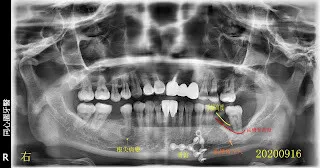

假牙材質2臨床案例...不同的假牙材質+牙齦萎縮

我忘了這位病人後來是否有來做後續的治療,我猜應該是沒有,因為我沒印象。但我那時都已經幫他精心劃好治療計畫的圖(方便他理解龐大的工程,對,這就像預售屋之類的藍圖)。 就不浪費了,剛拿來紙上談兵,模擬計畫,what if一下。